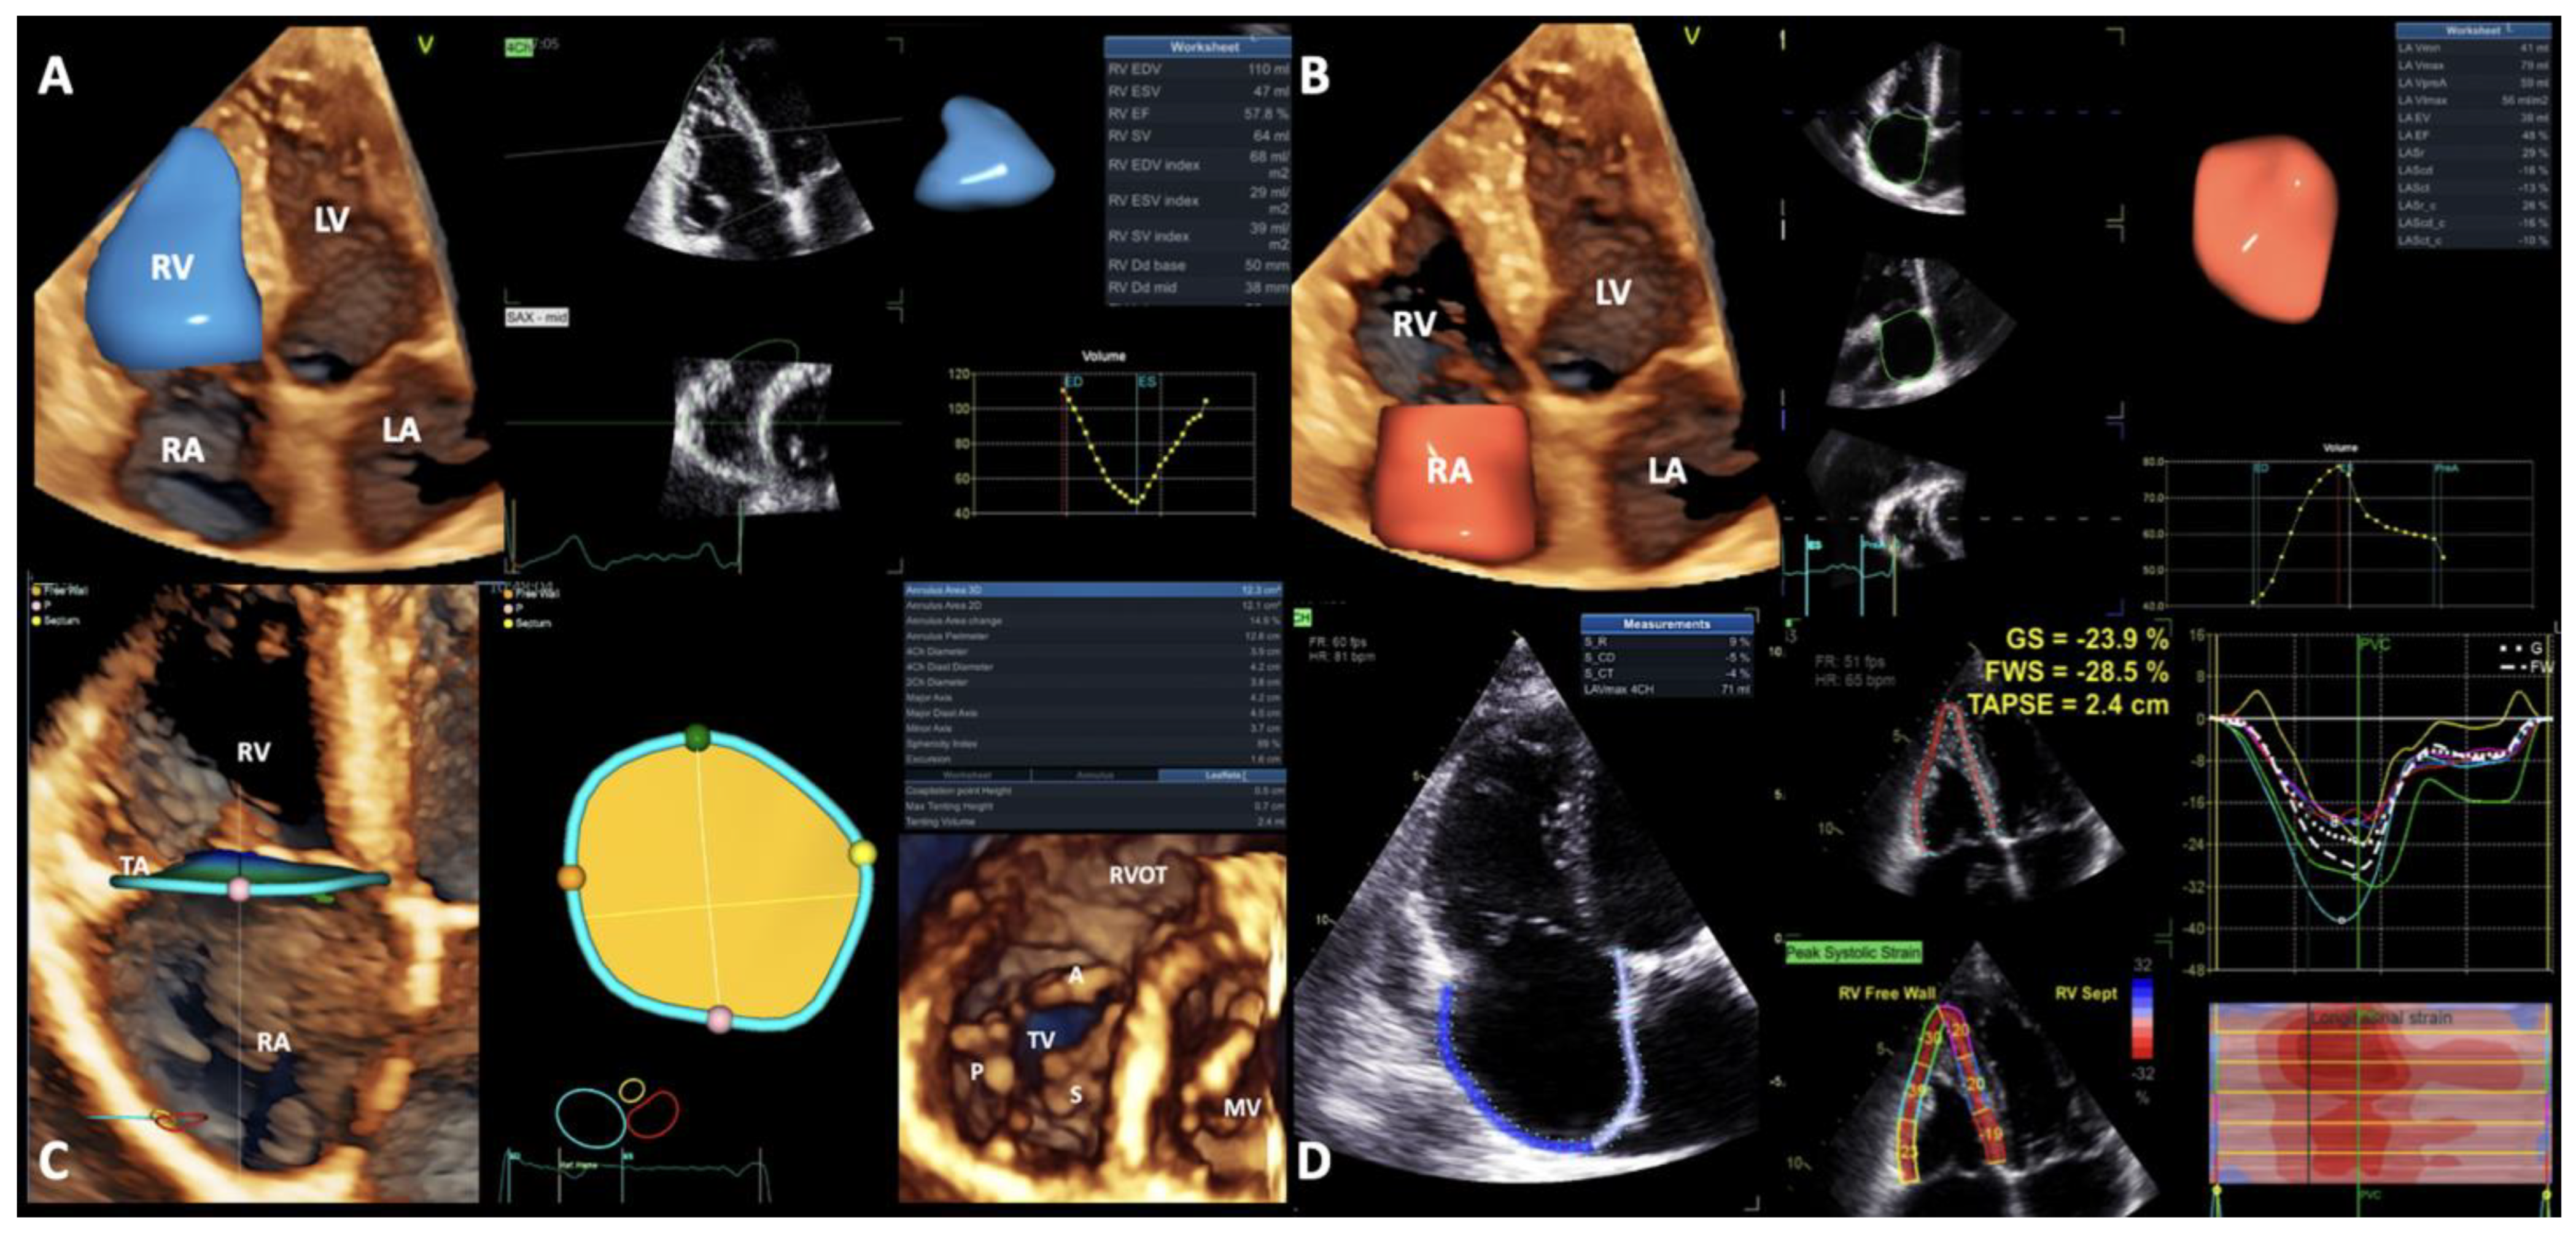

2.3. Echocardiographic Acquisitions and Analysis

3.1. Assessment of RV Size and Function (Table 2)

3.2. Assessment of RA Size and Function (Table 2)

3.3. Assessment of TA Size and Function (Table 2)

3.4. Correlations between the Echocardiographic Parameters